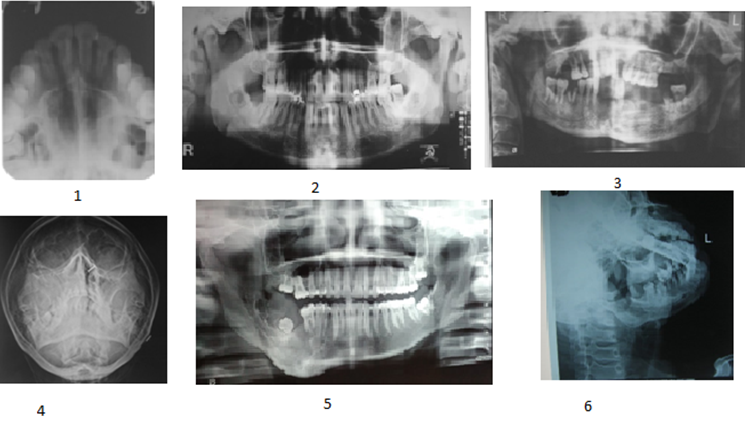

The most common site of occurrence in our documented cases is mandibular alveolar ridge (3 cases) followed by palate (2 cases) and one in sub mandibular gland (Figure 1). The female: male ratio was 1:1. Out of 2 cases reported here with a palatal swelling, 1 case presented with a dome shaped swelling and a bluish hue while the other one presented with an exophytic growth crossing the midline and areas of ulceration. In all the cases occurring in palate, the swelling was firm, and aspiration was found to be negative. In the cases occurring in the mandible, two cases occurred in the lingual aspect of the mandibular alveolar ridge and one in the anterior region. Out of the three cases occurring in mandible, one presented with a pedunculated growth arising from the lingual aspect of 45 and 46, other one only revealed the presence of a firm swelling in the lingual aspect of mandible distal to 47 with an inferior extension up to the base of the tongue and the last case in mandible revealed a large sessile mass extending from 42 till 37 with bony involvement. The remaining one case reported in this paper occurred in the left submandibular gland with involvement of level 2 and 3 lymph nodes of left side. The lesion occurring for longer duration was found to be low grade MEC to intermediate grade MEC.

The Radiological features (Figure 2) revealed fuzziness in the maxillary sinus in one of the two cases of MEC involving the palate. The other palatal case of MEC revealed no bony involvement. The cases involving the mandibular regions showed mild to moderate bony involvement. 3 of the cases of MEC revealed a well differentiated tumor primarily made up of mucous cells and epidermoid cells with no significant pleomorphism, mitoses and tumor necrosis. The histological grading of these 3 cases was low grade MEC. 2 cases documented here were diagnosed as intermediate grade as both the tumours were solid rather than cystic and irregular with predominance of intermediate cells and some mucous cells. One clear cell variant of MEC also has been presented here which revealed predominance of clear cells along with mucous and epidermoid cells (Figure 3).